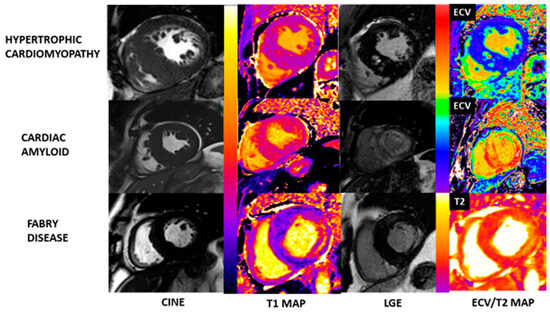

5.3. Tissue Characterization (Multiparametric Mapping and Late Gadolinium Enhancement Imaging)—Differentiating HCM Phenocopies

- Nordin, S.; Kozor, R.; Baig, S.; Abdel-Gadir, A.; Medina-Menacho, K.; Rosmini, S.; Captur, G.; Tchan, M.; Geberhiwot, T.; Murphy, E.; et al. Cardiac Phenotype of Prehypertrophic Fabry Disease. Circ. Cardiovasc. Imaging 2018, 11, e007168. [Google Scholar] [CrossRef]

- Sado, D.M.; White, S.K.; Piechnik, S.K.; Banypersad, S.M.; Treibel, T.; Captur, G.; Fontana, M.; Maestrini, V.; Flett, A.S.; Robson, M.D.; et al. Identification and assessment of anderson-fabry disease by cardiovascular magnetic resonance noncontrast myocardial T1 mapping. Circ. Cardiovasc. Imaging 2013, 6, 392–398. [Google Scholar] [CrossRef]

- Moon, J.C.; Sheppard, M.; Reed, E.; Lee, P.; Elliott, P.M.; Pennell, D.J. The histological basis of late gadolinium enhancement cardiovascular magnetic resonance in a patient with anderson-fabry disease. J. Cardiovasc. Magn. Reson. 2006, 8, 479–482. [Google Scholar] [CrossRef]

- Fontana, M.; Pica, S.; Reant, P.; Abdel-Gadir, A.; Treibel, T.A.; Banypersad, S.M.; Maestrini, V.; Barcella, W.; Rosmini, S.; Bulluck, H.; et al. Prognostic Value of Late Gadolinium Enhancement Cardiovascular Magnetic Resonance in Cardiac Amyloidosis. Circulation 2015, 132, 1570–1579. [Google Scholar] [CrossRef]

- Swoboda, P.P.; McDiarmid, A.K.; Erhayiem, B.; Broadbent, D.A.; Dobson, L.E.; Garg, P.; Ferguson, C.; Page, S.P.; Greenwood, J.P.; Plein, S. Assessing Myocardial Extracellular Volume by T1 Mapping to Distinguish Hypertrophic Cardiomyopathy From Athlete’s Heart. J. Am. Coll. Cardiol. 2016, 67, 2189–2190. [Google Scholar] [CrossRef]

- Nordin, S.; Kozor, R.; Bulluck, H.; Castelletti, S.; Rosmini, S.; Abdel-Gadir, A.; Baig, S.; Mehta, A.; Hughes, D.; Moon, J.C. Cardiac Fabry Disease With Late Gadolinium Enhancement Is a Chronic Inflammatory Cardiomyopathy. J. Am. Coll. Cardiol. 2016, 68, 1707–1708. [Google Scholar] [CrossRef]

- Augusto, J.B.; Nordin, S.; Vijapurapu, R.; Baig, S.; Bulluck, H.; Castelletti, S.; Alfarih, M.; Knott, K.; Captur, G.; Kotecha, T.; et al. Myocardial Edema, Myocyte Injury, and Disease Severity in Fabry Disease. Circ. Cardiovasc. Imaging 2020, 13, e010171. [Google Scholar] [CrossRef]

- Abdel-Aty, H.; Cocker, M.; Strohm, O.; Filipchuk, N.; Friedrich, M.G. Abnormalities in T2-weighted cardiovascular magnetic resonance images of hypertrophic cardiomyopathy: Regional distribution and relation to late gadolinium enhancement and severity of hypertrophy. J. Magn. Reson. Imaging 2008, 28, 242–245. [Google Scholar] [CrossRef]